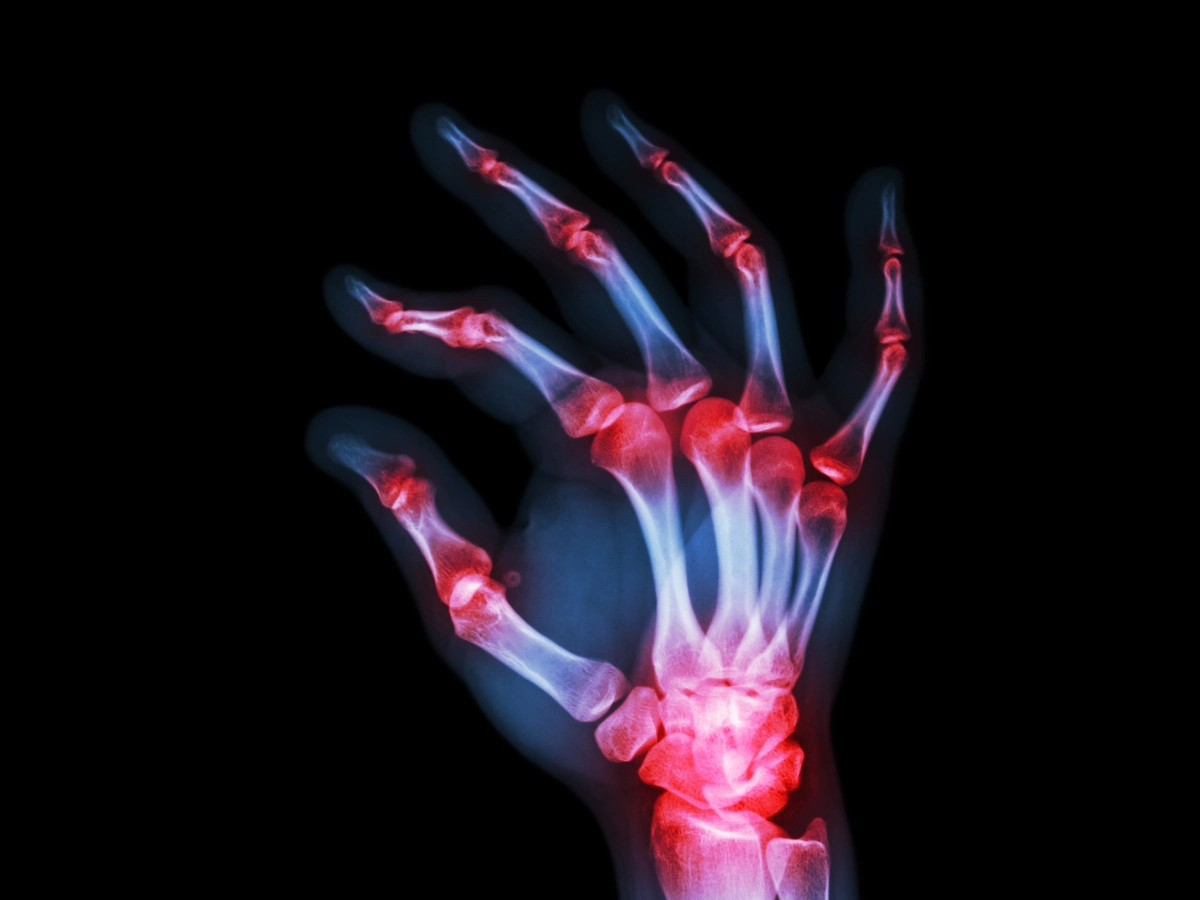

손가락 관절염 증상 및 치료법

뼈와 뼈 사이에는 마찰을 막아주며 관절이 원활하게 움직일 수 있도록 연골, 활막, 인대, 관절낭 등이 분포하고 있는데요.

관절의 반복적 사용으로 연골이 닳거나 다른 원인들에 의해 관절 사이 및 관절에 염증이 생기게 될 경우 통증과 붓기 등을 동반하는 것을 관절염이라고 합니다.

손가락 관절염은 손가락 관절 부분에 관절염이 발생한 것으로, 손가락을 움직일 때 운동 제한과 통증이 발생하기도 합니다.

특히 손가락 관절은 자주 사용하는 부위이며 다른 관절보다 약한 부위인 만큼, 손가락 관절염 증상을 방치할 경우 일상생활에 큰 불편함을 느끼게 될 수 있고 심지어는 손가락 모양의 변형을 초래할 수 있습니다.